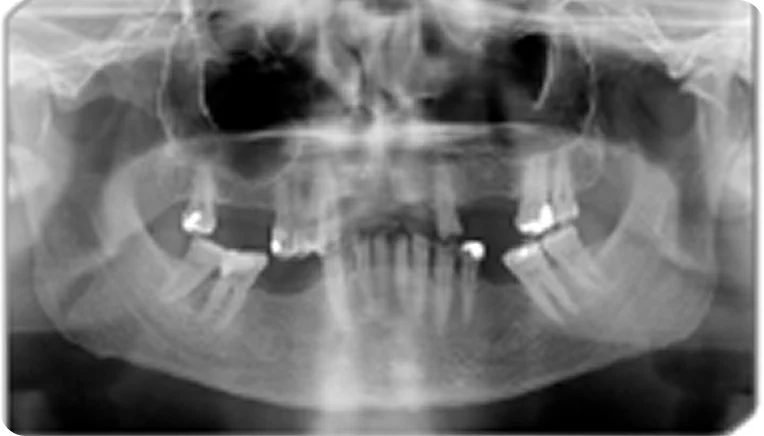

Данные пациента [гипотетический пациент]:

Геннадий, 55 лет

• 1 класс по Кеннеди ВЧ, моляры и премоляры верхней челюсти утеряны в результате осложненного кариеса;

• зубная формула представлена справа.